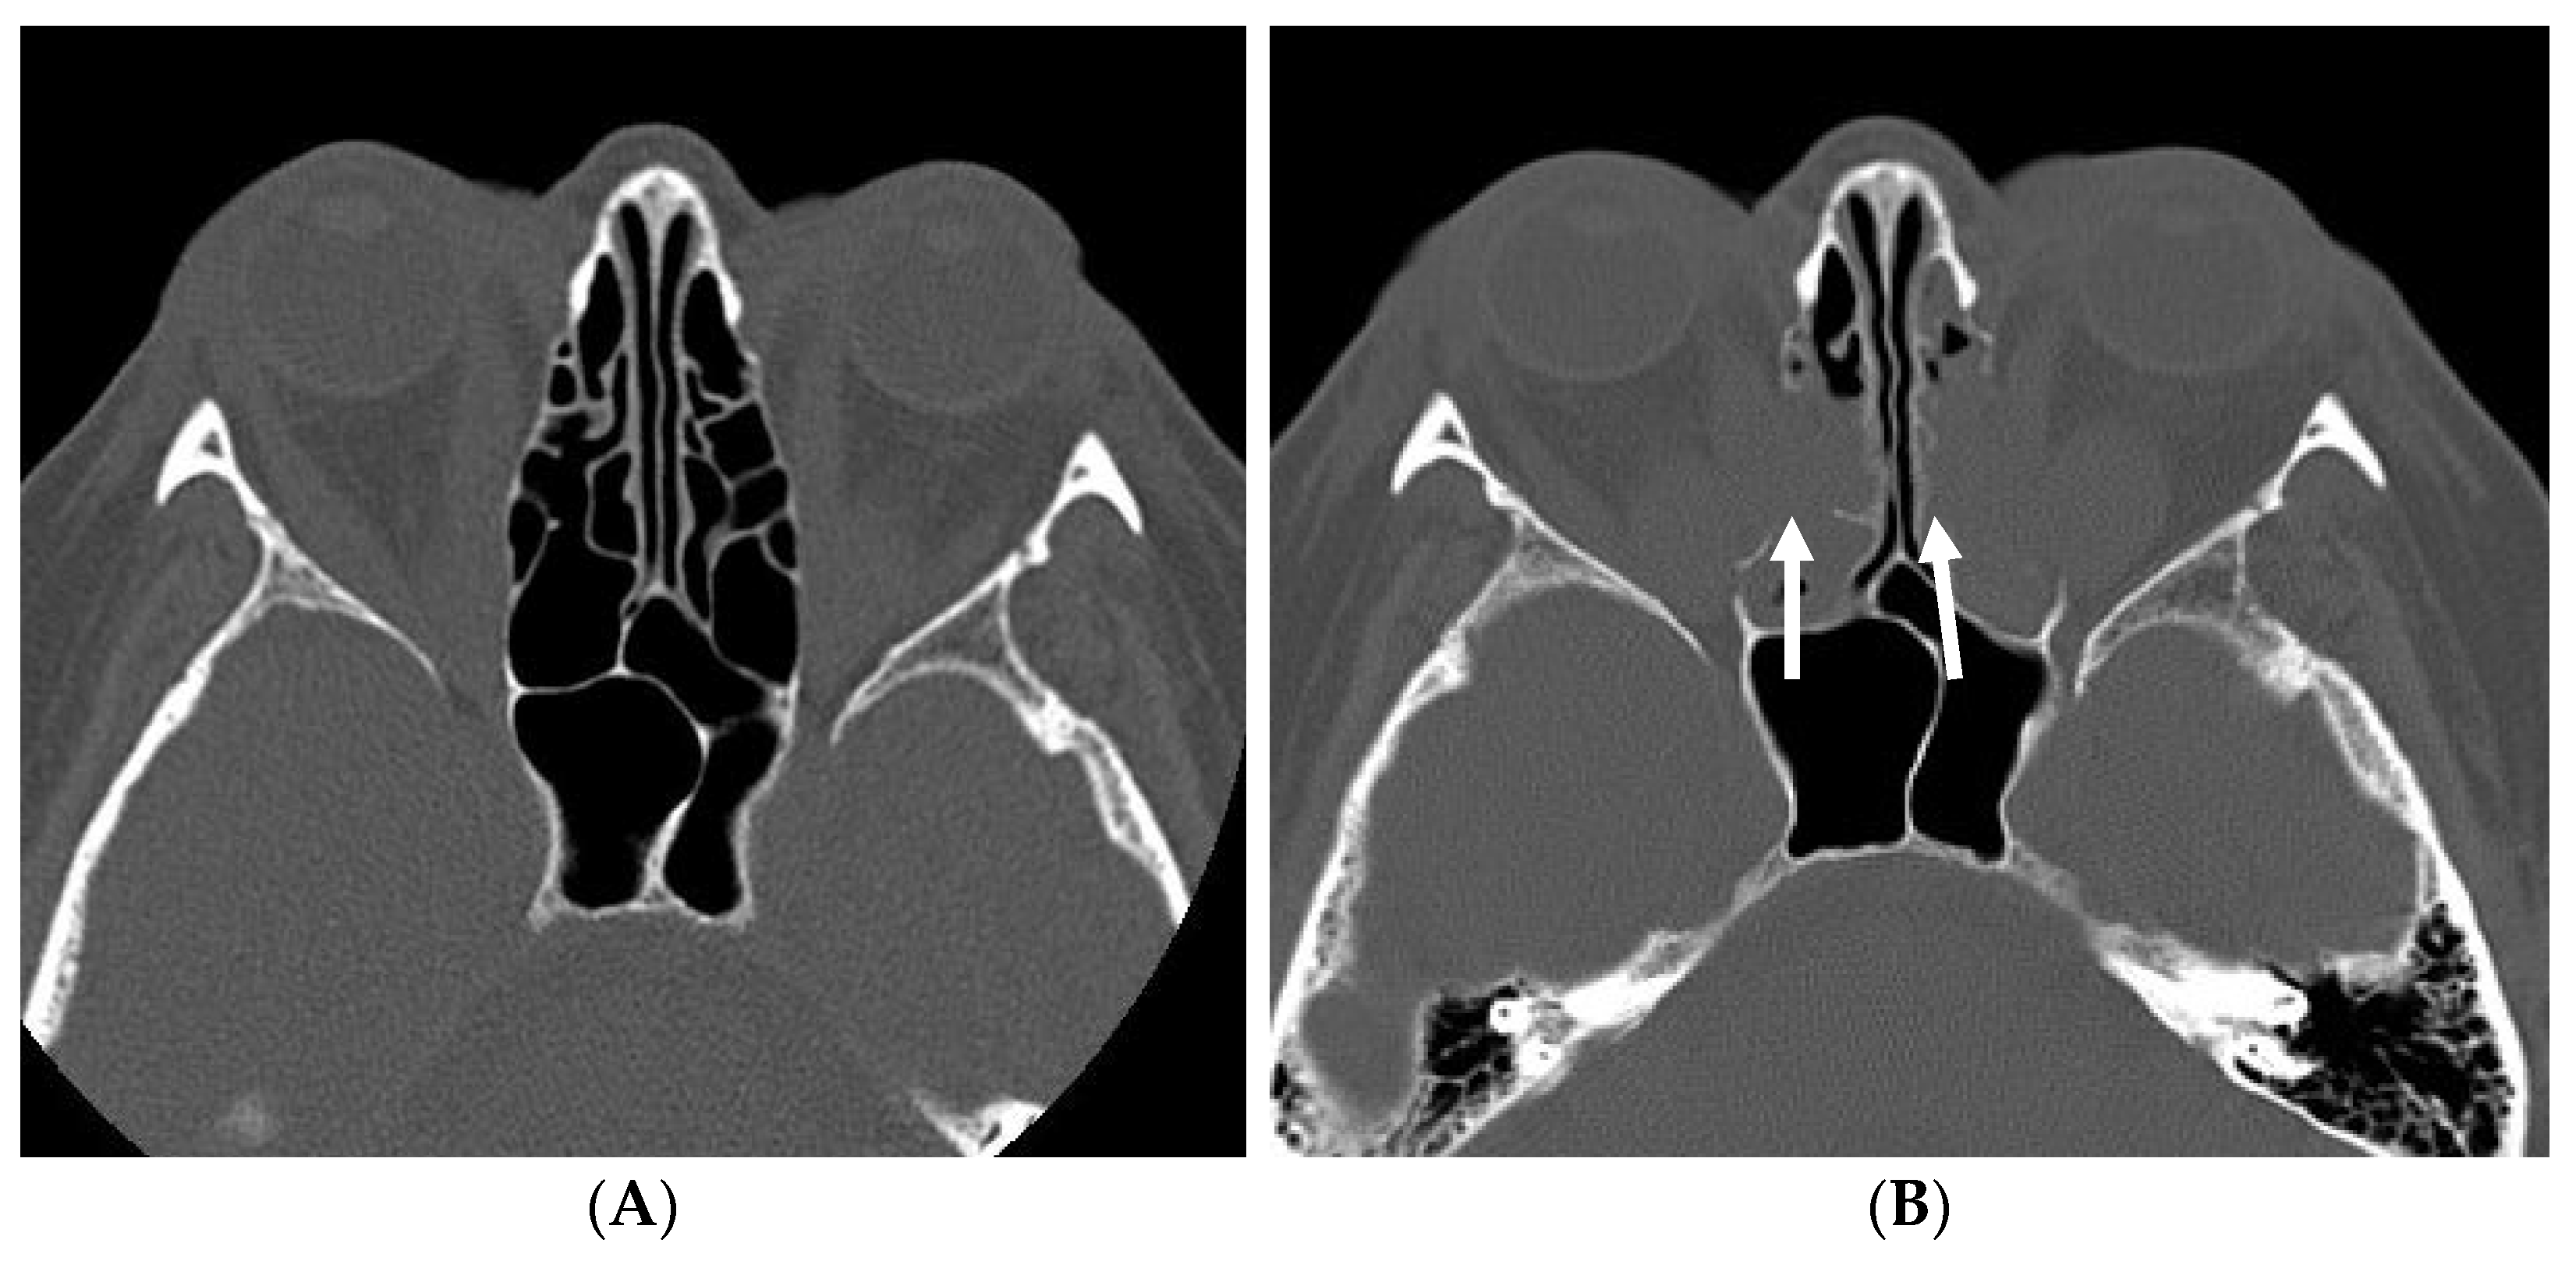

2.1. Surgical Technique